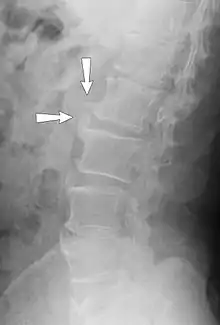

Osteophytes form naturally on the back of the spine as a person ages and are a clinical sign of degeneration in the spine. In this case, the osteophytes are commonly not the source of back pains, but instead are a sign of an underlying problem. However, osteophytes on the spine can impinge on nerves that leave the spine for other parts of the body. This impingement can cause pain in both upper and lower limbs and a numbness or tingling sensations in the hands and feet because the nerves are supplying sensation to their dermatomes. [6]